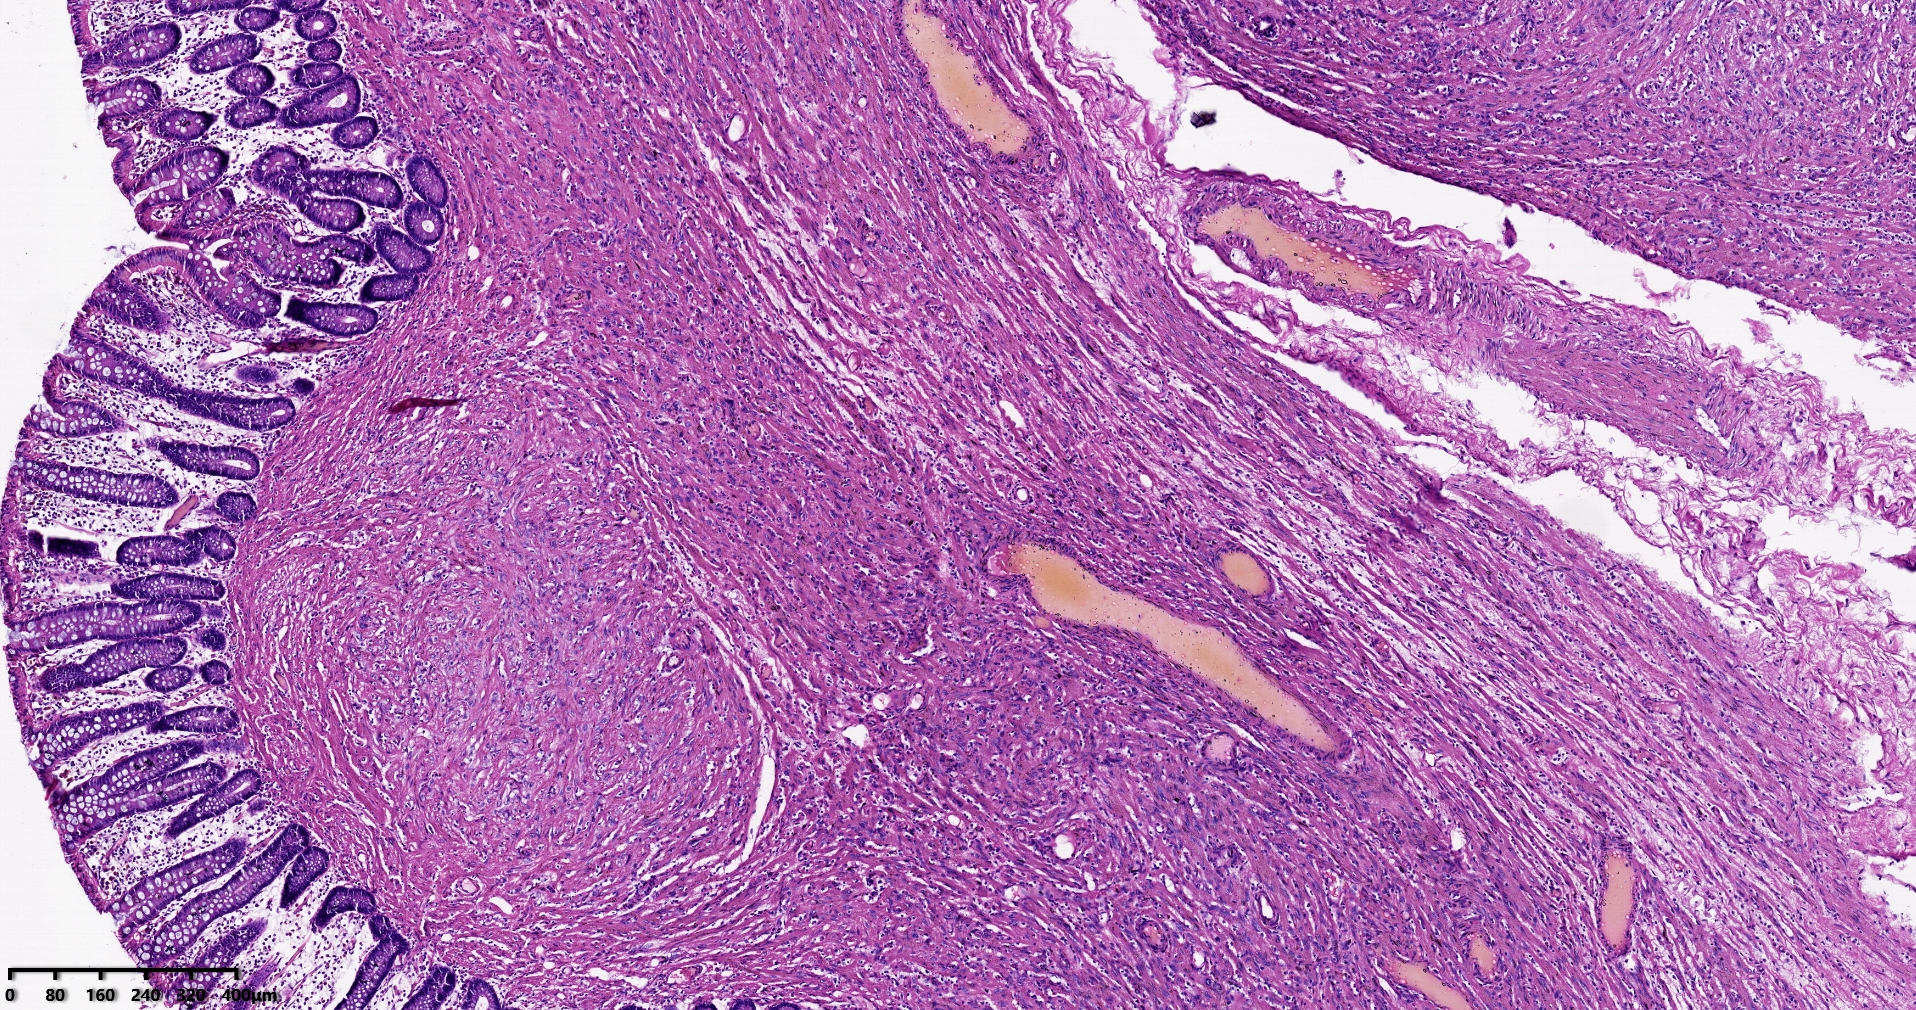

结肠肝曲息肉状肿物,平滑肌瘤?胃肠道间质瘤?炎性纤维性息肉?

性别

男

年龄

56岁

临床诊断

结肠肝曲息肉

一般病史

不详

标本名称

大体所见

灰红色椭圆形息肉一个,直径2.5cm,蒂长0.5cm,切面灰白灰红色,质中。

请路过的老师指教。

考虑间质瘤?

就HE形态而言,间质瘤的可能性要大一些,建议做免疫组化协助鉴别。